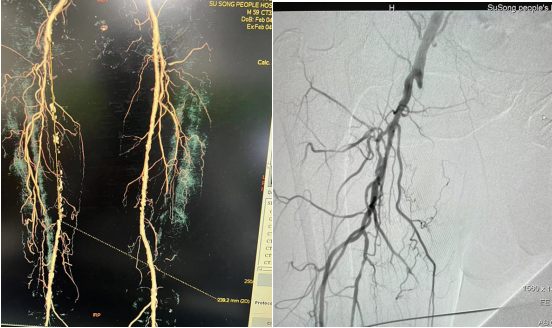

患者男、59岁,以“右下肢胀痛4月余”入住康复医学科,既往有高血压、糖尿病史多年,一直未规律服用药物。入院行下肢血管彩超检查发现右下肢股动脉血栓伴闭塞,行右下肢动脉CTA检查诊断右侧股浅动脉长段(约24cm)闭塞,如果得不到及时治疗,将来闭塞逐渐加重,继而可出现下肢缺血坏死、溃疡形成,严重时引起肢体功能障碍。

经康复医学科、医学影像中心等多科室讨论,并与患者及家属充分沟通征得同意,2月7 日下午14:00在上级专家指导下行右下肢动脉造影加血管成形术的介入治疗。术中开通闭塞段血管逐段行球囊扩张,并置入两枚动脉血管支架。术后造影右下肢血流畅通,患者症状亦明显改善。